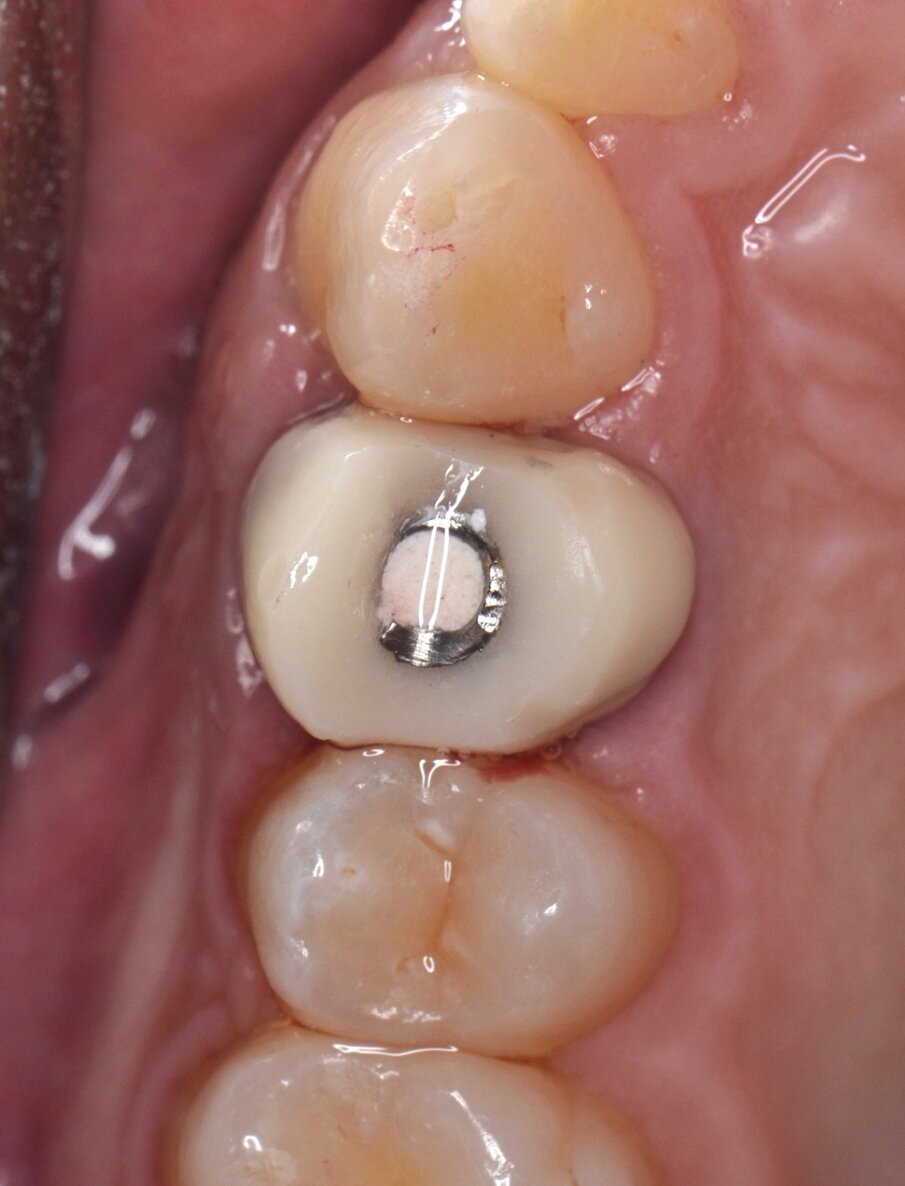

All’esame obiettivo viene si evidenzia una frattura verticale a carico dell’elemento in questione (Figg. 1, 2) che pone indicazione assoluta all’estrazione dentaria; per evitare di aggravare l’inevitabile contrazione della cresta ossea alveolare, si decide di eseguire l’estrazione dell’elemento fratturato senza sollevare alcun lembo. Viene effettuato un esame radiografico endorale allo scopo di visualizzare la morfologia della radice dentaria e i suoi rapporti con le strutture viciniori. (Fig. 3)

Fig. 1 - Elemento 1.4 fratturato (visione occlusale).

Fig. 17 - Corona provvisoria in resina ribasata sul moncone provvisorio (visione occlusale).

Fig. 24 - Corona protesica definitiva in zirconia stratificata (visione occlusale).